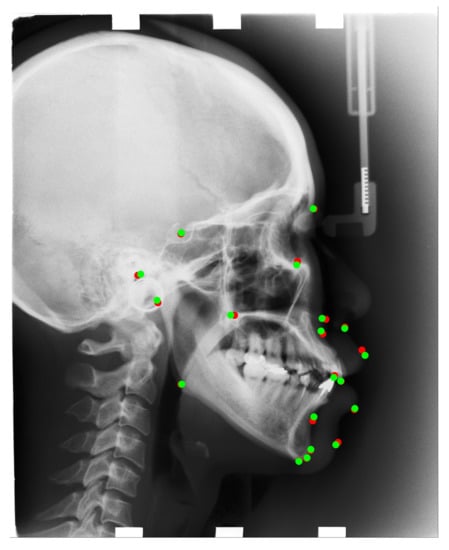

After registration, we copy the landmark locations of the reference images (training images) to moving images (test images). We consider the landmark location of a reference image as the center of the ROI patch, extract a 512 × 512 resolution patch image on the moving image, and then resize it to a 256 × 256 resolution patch for the test. The extracted images will be treated as input to our trained convolutional neural network (CNN); thus, we can detect the corresponding landmark in the patch image. The registration results are presented in Figure 5.

Figure 5. In the image, we take the reference image’s landmarks(Training images) as center of the patch image, then we draw a bounding box (ROI) in the test image, as the input to our corresponding trained models. Red dots are the reference images’ landmarks, green dots are test image’s landmarks, which are the landmarks we aim to detect.